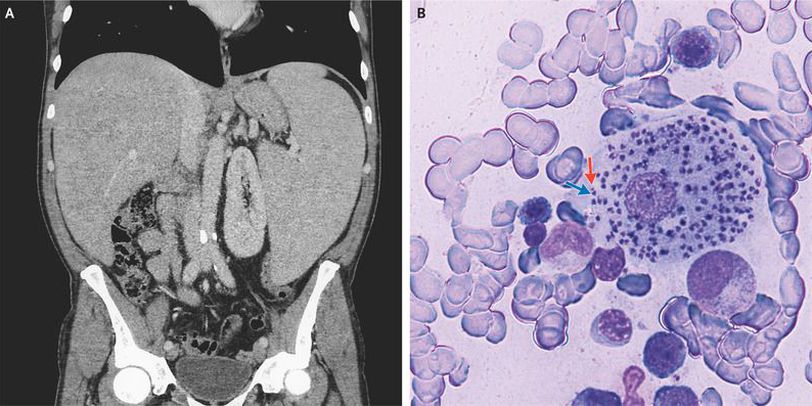

A 49-year-old previously healthy man presented to the emergency department with a 5-month history of fever, abdominal pain, fatigue, and an unintentional 15-kg weight loss. The physical examination was notable for an enlarged liver and spleen. Laboratory studies showed a white-cell count of 2040 per cubic millimeter (reference range, 4000 to 10,000), a hemoglobin level of 9.2 g per deciliter (reference range, 14.0 to 18.0), and a platelet count of 50,000 per cubic millimeter (reference range, 140,000 to 400,000). Blood cultures as well as tests for human immunodeficiency virus, hepatitis B virus, hepatitis C virus, cytomegalovirus, and Epstein–Barr virus were negative. Computed tomography of the abdomen confirmed the presence of an enlarged liver and markedly enlarged spleen (Panel A). Examination of a bone marrow aspirate revealed amastigotes, each with a nucleus (Panel B, blue arrow) and a kinetoplast (Panel B, red arrow), within histiocytes. This is the typical appearance of leishmaniasis, and polymerase-chain-reaction testing of the bone marrow aspirate confirmed the diagnosis. Transmitted by sandflies, Leishmania infantum is endemic to Italy and the Mediterranean region. The patient started treatment with liposomal amphotericin B. At a follow-up visit 1 month later, the fever, abdominal pain, and fatigue had resolved, and physical examination revealed resolution of the splenomegaly.